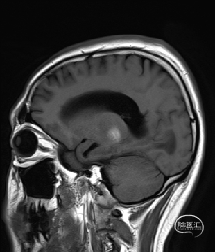

病人有二次左侧丘脑出血病史,第一次出血量少,非手术治疗;入院前一周,再次发生出血,并继发梗阻性脑积水;

术前MRI检查提示左侧丘脑中脑海绵状血管瘤并卒中,梗阻性脑积水;

年轻患者,较短时间内发生左侧丘脑二次出血,出现右侧面部及上肢麻木,复视,第二次出血后并发梗阻性脑积水,出现头痛。结合病史、神经系统体征、头颅CT及MRI检查,诊断左侧丘脑及中脑CM并卒中、脑积水明确,并导致了神经功能障碍,具备手术指征。

丘脑和脑干的海绵状血管瘤较为常见,由于病变位置深,手术不易显露,即便显露,操作空间狭小,且为重要的神经功能区,手术难度及风险大,根据病变的位置,常见的入路有经半球间纵裂入路、额眶颧入路、颞下入路、枕下经小脑幕入路、幕下小脑上入路。

本例患者磁共振检查清晰显示病变位于左侧丘脑中脑区域,且位于丘脑内下方向中脑顶盖延续,病变的上部、前部、外侧部都有重要的神经组织,因此,手术从上方、前方、外侧方向切除病变均难以实施;

从后方有POPPEN入路、Krause入路等,但是因为病变并未充分向松果体区、大脑大静脉后方突出,有大脑大静脉复合体的阻挡,POPPEN入路有较大的难度显露及切除病变,残留的可能性比较大;传统显微镜下进行的幕下小脑上入路在病变的显露及切除上依然有较大的难度。

综上,病变位于左侧丘脑及中脑,传统的手术入路或者显微手术方法有极大的难度和风险;